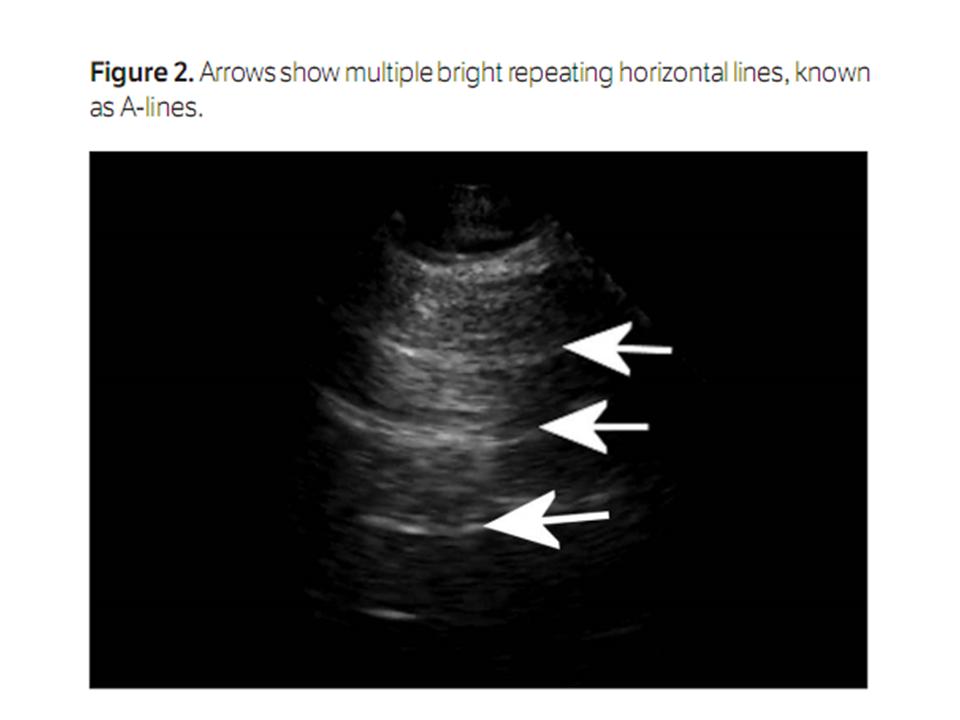

reflecting nearly 80% of the ultrasonic beam it encounters. As seen with other

anatomic structures with high impedance, horizontal reverberation artifacts are

readily created and are known as A-lines in the lung ultrasound lexicon (Figure 2). The

Figure

2.

Arrows show multiple bright repeating horizontal lines, known as

A-lines.